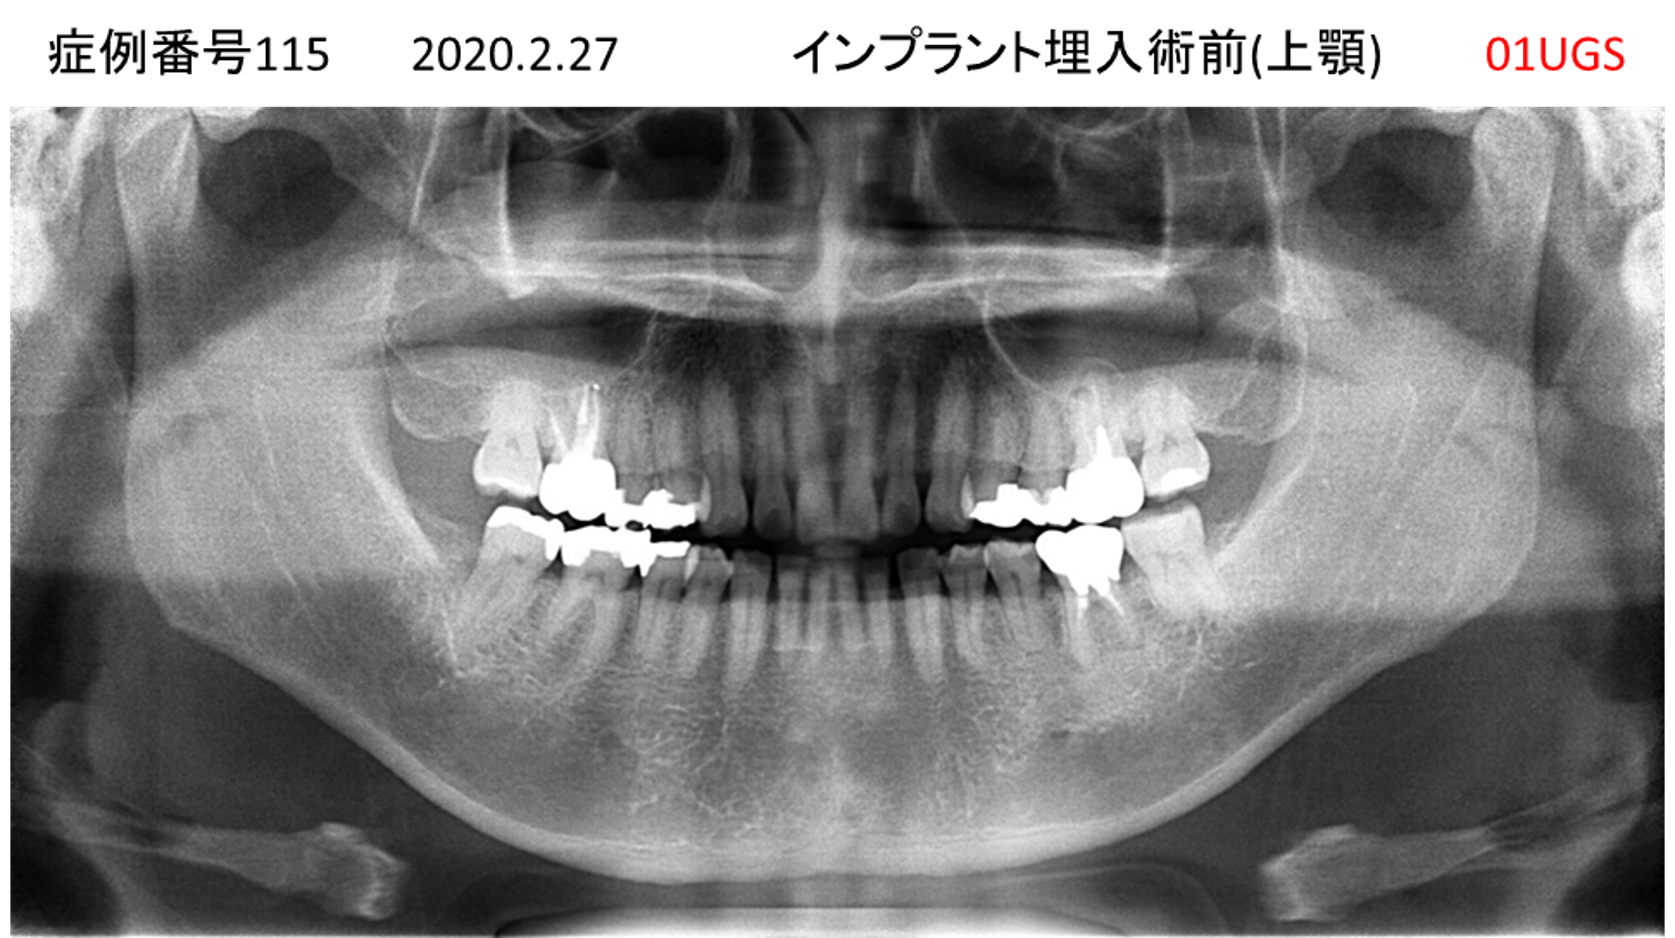

義歯が合わない、噛めない患者様のインプラント症例

| 治療名称 |

インプラントコーヌステレスコープ |

| 治療費用 |

270万円+税 |

| 治療期間 |

4か月 |

| 患者さんの症状(主訴) |

義歯が合わない、噛めない |

| 治療内容 |

インプラント、義歯作製(コーヌステレスコープ) |

| 治療結果 |

しっかり噛めるようになった。見栄えが良くなった。 |

| 治療の注意点(リスク/副作用) |

義歯が壊れた場合、インプラントが壊れた場合は再治療が必要 |